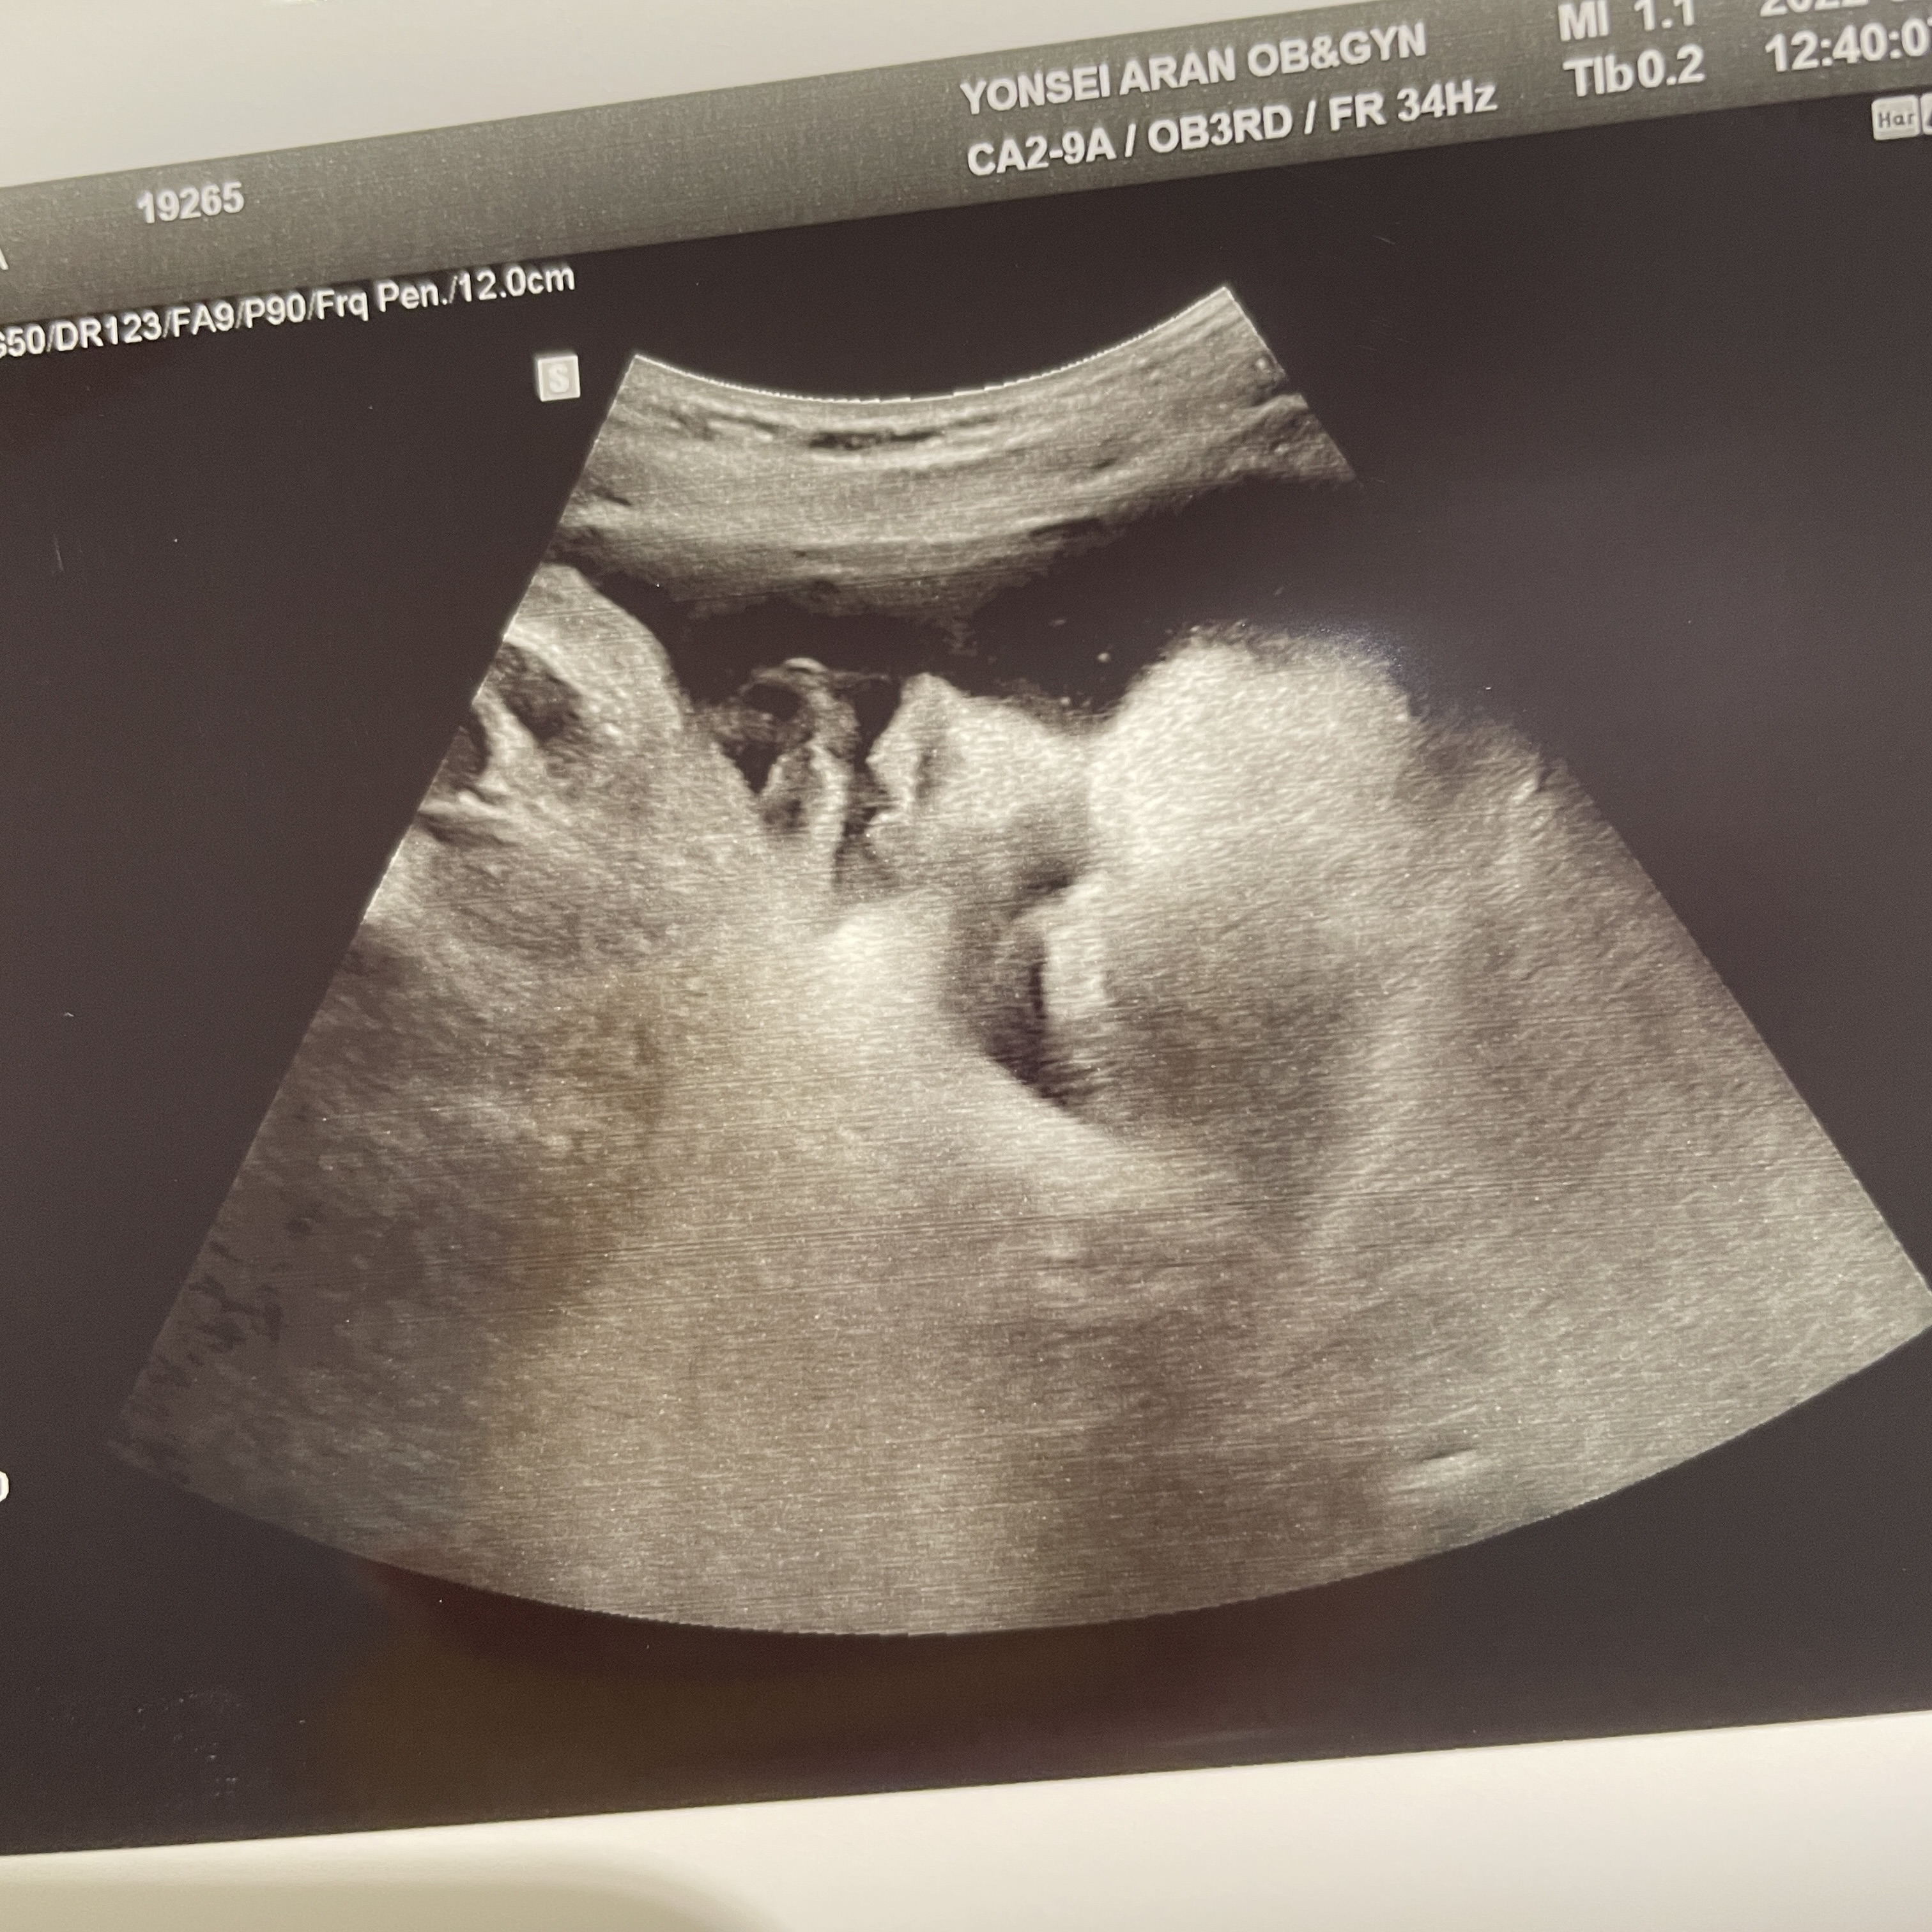

초음파 기기

초음파 사진이 선명하게 잘 나오는 편이었다.

그리고 애기 초음파 사진도 진짜 이쁘게 여러장 찍어주신다.

덕분에 내 태교 다이어리는 초음파 사진들로 풍년이다ㅎㅎ